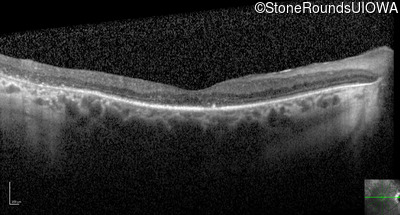

Optical Coherence Tomography - Left - 20/30 +2

Exemplar / OCT Stack

OCT Stack